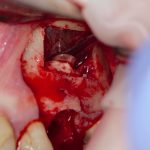

Я зафиксировал костный блок практически без адаптации на несколько винтов. Обрати внимание, что винты находятся в зоне, где не планируется установка имплантатов. Фиксация должна быть надежной, поскольку мне еще предстояла подготовка лунок для имплантатов. Трех винтов для этого вполне достаточно.

Дальнейшая адаптация костного блока свелась к сглаживанию острых краев. После чего я приступил к подготовке лунок и установке имплантатов.

Установка имплантатов.

Напомню, что для этой работы я выбрал субкрестальные имплантаты Ankylos C/X. Они прекрасно сочетаются с любым методом остеопластики.